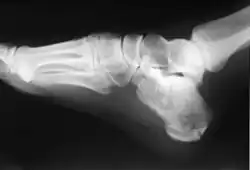

In humans and many other primates, the calcaneus (/kælˈkeɪniəs/; from the Latin calcaneus or calcaneum, meaning heel;[1] pl.: calcanei or calcanea) or heel bone is a bone of the tarsus of the foot which constitutes the heel. In some other animals, it is the point of the hock.

In humans, the calcaneus is the largest of the tarsal bones and the largest bone of the foot. Its long axis is pointed forwards and laterally.[2] The talus bone, calcaneus, and navicular bone are considered the proximal row of tarsal bones.[3] In the calcaneus, several important structures can be distinguished:[3]

The calcaneus is part of two joints: the proximal intertarsal joint and the talocalcaneal joint. The point of the calcaneus is covered by the calcanean bursa.